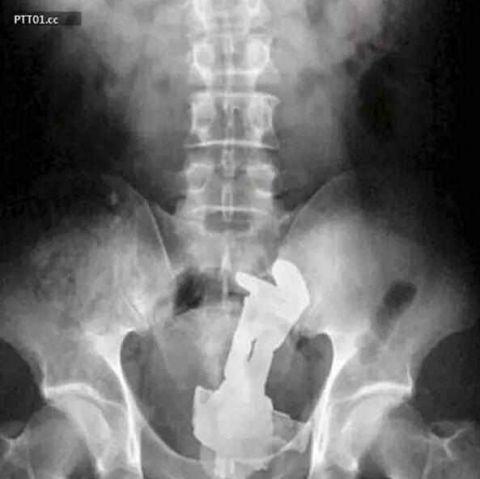

这玩意儿是自己插进去的